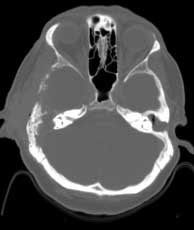

CT bone windows

CT ax BW